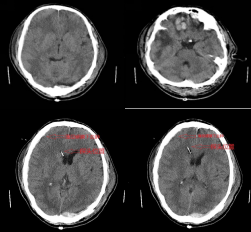

2021年01月15日,突如其来的意外打破了患者桑某一家的平静生活,39岁的患者桑某不慎从3米高的楼上摔下,当即昏迷,家属立即送患者至阿坝州人民医院神经外科住院治疗,由值班医生详细询问病史和全面查体后诊断为“重型闭合性颅脑损伤:1.左侧枕部小脑骑跨性硬膜外血肿;2.双侧额叶脑挫裂伤。由于患者颅内出血量较大,随时可能病情加重甚至危机生命,介于患者颅内多出损伤,且相当严重,值班医生立即上报了文家智副主任医师,文医生得知患者病情后第一时间赶到科室,进一步掌握患者病情后,建议患者需要立即行手术治疗,家属焦急万分,一时拿不定主意,主管医生耐心与患者家属沟通解释病情,并分析手术利弊,逐步取得了家属信任,决定接受医生建议同意手术。

由于血肿位置特殊,手术区域临近重要血管,如若损伤可能危机生命,较普通手术有一定难度。由于术前手术医师的充分准备和术中对重要血管的保护,经过五个小时的手术治疗,手术顺利成功完成,患者术后转入了医院重症监护室进一步监护治疗。术后复查颅脑CT发现,患者原本双侧额叶的脑挫伤出血增多,为保证患者生命安全和避免多次手术及巨额治疗费用,经科室讨论,放弃以往的“骨瓣减压术”手术方式而选择了现国内外推荐可行的“颅内压监测/脑室外引流术”,该手术技术在神经外科已成熟并已经成功救治多例患者。主管医生再次向家属详细 病情及下一步治疗方案并同时了解到患者家庭经济困难,于是安抚患者家属的同时宣传阿坝州医保政策,包括大病医疗补助,水滴筹多种方式来解决经济困难以救治患者,患者家属焦虑的心情得以平复,经过商议和医生们的充分准备,患者顺利进行了第二次手术治疗。

患者在第二次手术治疗后复查恢复情况良好,患者手术中置入了颅内颅内压探头,该探头对患者颅内压进行了实时监测,保障了患者顺利度过危险期,病情逐渐平稳。住院期间政府相关部门及医院领导多次到病房关心慰问患者,经过医院医护人员对患者的精心救治及家属的辛勤照顾下,患者恢复良好,顺利出院。